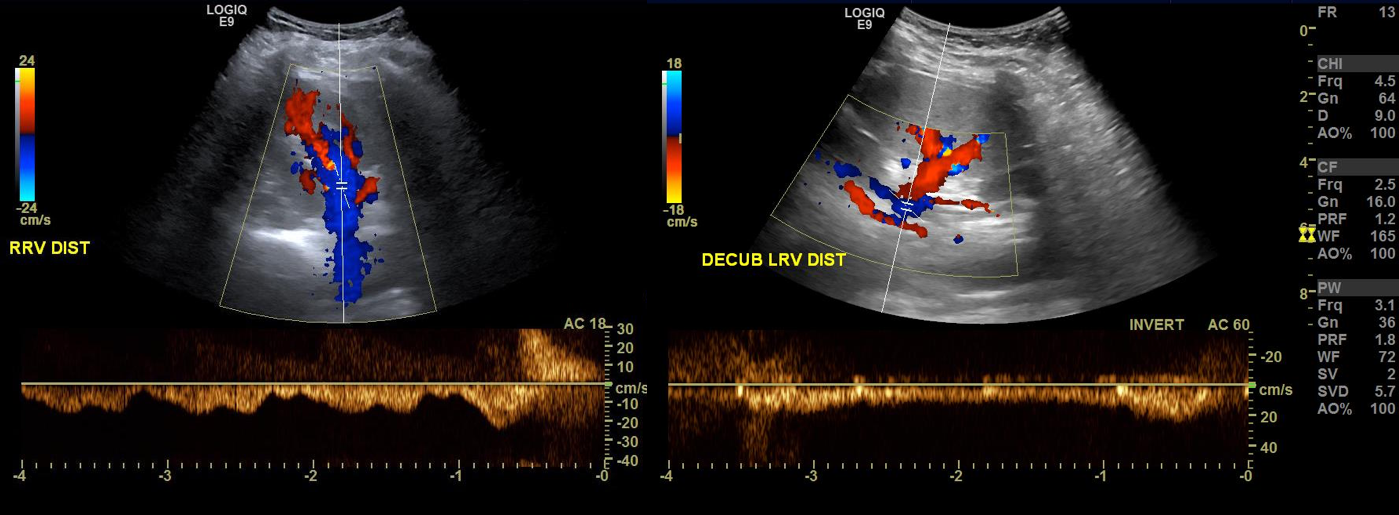

Duplex showed the narrowing in the left renal vein and spectral Doppler showed elevated velocities across the compression caused by the superior mesenteric artery (below). The collecting system was not obstructed.

venous duplex14.jpg

On the duplex, the proximal left renal vein (LRV) was not visualized. The right kidney had normal parenchymal appearance and blood flows, while the left, the kidney appeared distended and had flows consistent with outflow obstruction.

spectral kidneys

Spectral Doppler flows show respirophasicity in right renal vein(RRV), outflow obstruction on left renal vein (LRV)